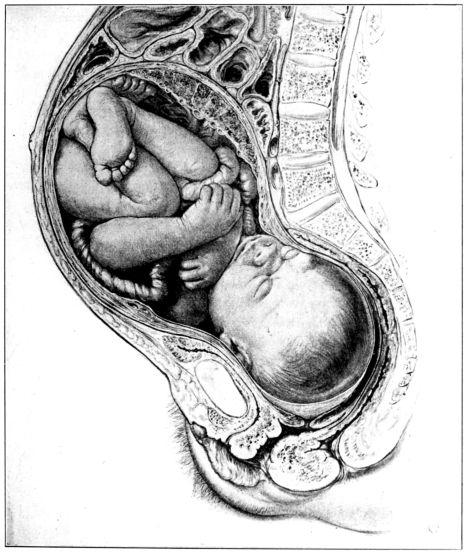

27. Full term fetus in utero 81

50. Attitude of fetus in uterus at term 217

51. Illustration from first text-book on obstetrics 218